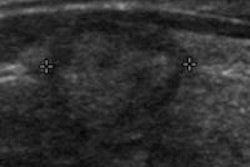

A team led by Dr. Brian Mott of Oregon Health and Science University found that MCE with custom-designed phosphatidylserine-enriched microbubble contrast could bind to injured heart tissue to detect molecular changes that occurred up to six hours after a very brief reduction in blood flow.

The method could allow clinicians to detect problems at the bedside in minutes, and it could also be used to judge patient risk for a heart attack based on the size of the area that is jeopardized by low blood flow, according to the researchers.